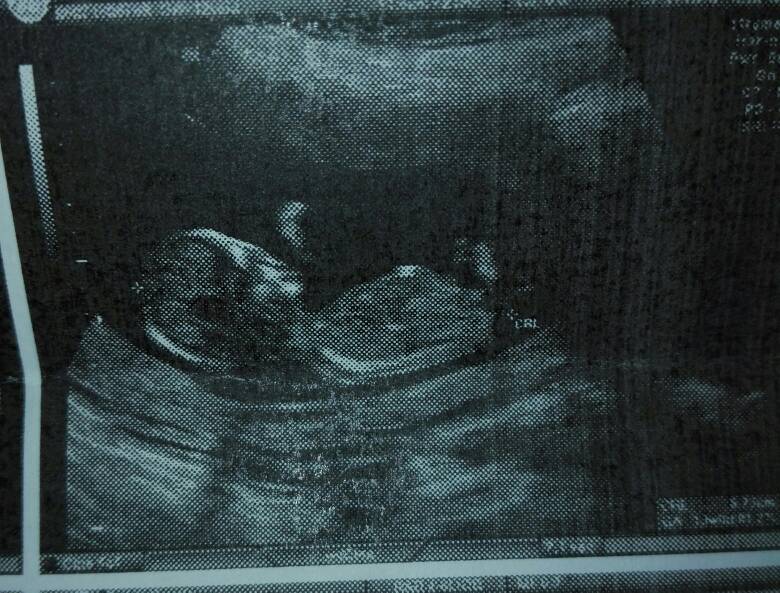

Ja wczoraj miałam prenatalne, dzidzia miala juz 6,6cm, zdrowa, wszystko na swoim miejscu, ryzyka chorob niskie wszystko jest ok [emoji173] no i według doktorka na takie 93% dziewczynka [emoji173][emoji173]

Ja wczoraj miałam prenatalne, dzidzia miala juz 6,6cm, zdrowa, wszystko na swoim miejscu, ryzyka chorob niskie wszystko jest ok [emoji173] no i według doktorka na takie 93% dziewczynka [emoji173][emoji173]Zobacz załącznik 920209